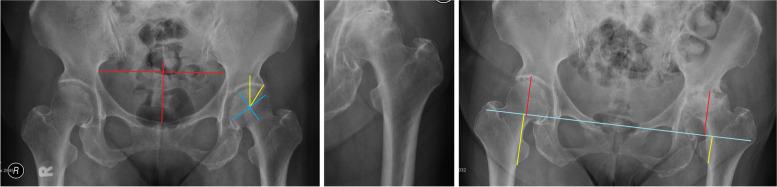

Diagnosis of hip RPOA was confirmed in 18 patients. Their mean age at surgery (72 years) was significantly higher in this group than in the dysplasia and avascular necrosis groups. The mean pelvic tilt parameter (0.485) of RPOA group was significantly lower than those of other groups. The mean initial Tonnis angle (8.35°) of RPOA group was significantly higher than those of avascular necrosis and osteoarthritis groups. The differences were statistically significant between RPOA and non-RPOA groups in limb shortening rate, superior joint space narrowing, acetabular destruction, and head destruction (P < 0.05). Tonnis angle and lateral subluxation also increased significantly during the disease progression.

18例患者被确诊为髋关节RPOA。该组患者的平均手术年龄(72岁)显著高于发育不良和股骨头缺血性坏死组。RPOA组的平均骨盆倾斜参数(0.485)显著低于其他组。RPOA组的平均初始托尼角(8.35°)显著高于股骨头缺血性坏死组和骨关节炎组。RPOA组与非RPOA组在肢体短缩率、上关节间隙变窄、髋臼破坏和股骨头破坏方面存在显著差异(P<0.05)。在疾病进展过程中,托尼角和外侧半脱位也显著增加。

结论

骨盆后倾和托尼角增加可能是RPOA发病机制的一部分,导致获得性髋臼倾斜和外侧半脱位逐渐加重。我们建议根据现有文献和当前研究结果制定现代综合诊断标准。建议进一步进行外部验证。